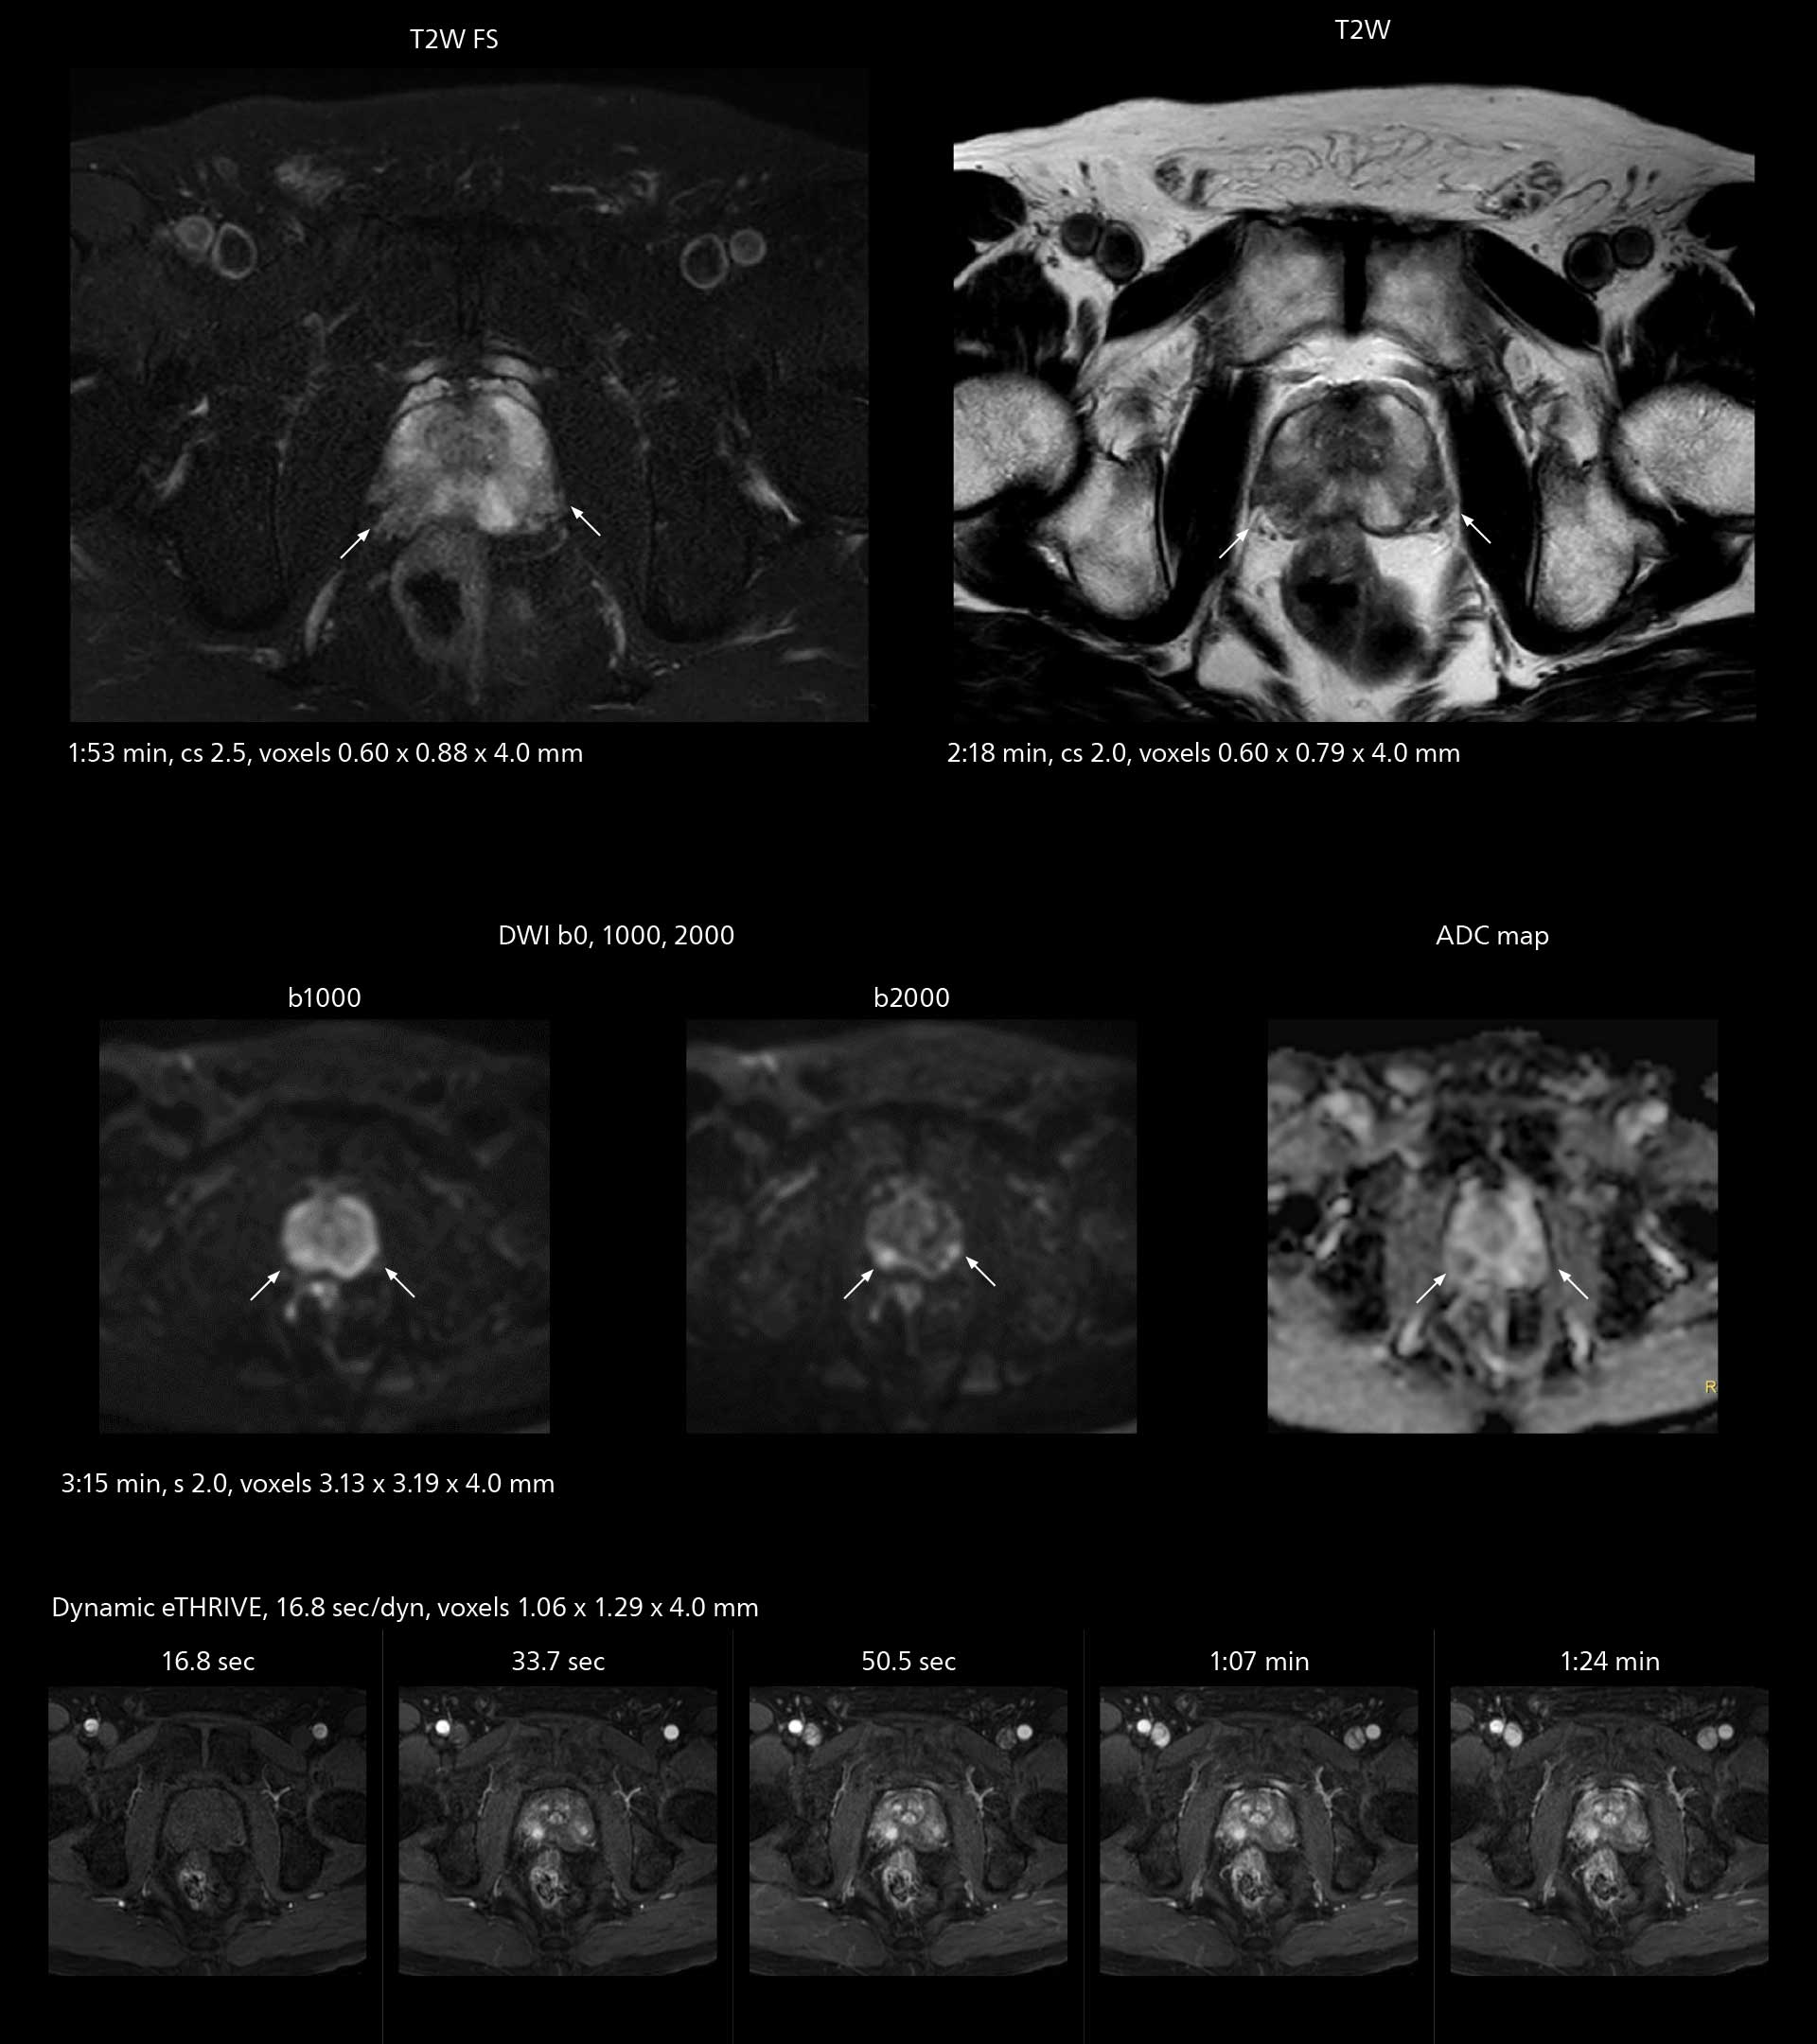

MRI of prostate

Examples of prostate imaging showing faster scan times and improved resolution illustrate the power of SmartPath to Elition X in this case of prostate cancer with PI-RADS score 4.

The high performance of the Vega HP gradients is particularly impressive in DWI. “The Vega HP gradients enable us to scan faster and use b-values as high as 2000, for example in prostate DWI and in DWIBS, which provides image quality that is remarkably improved over the previous system and we are able to more easily see lesions.”